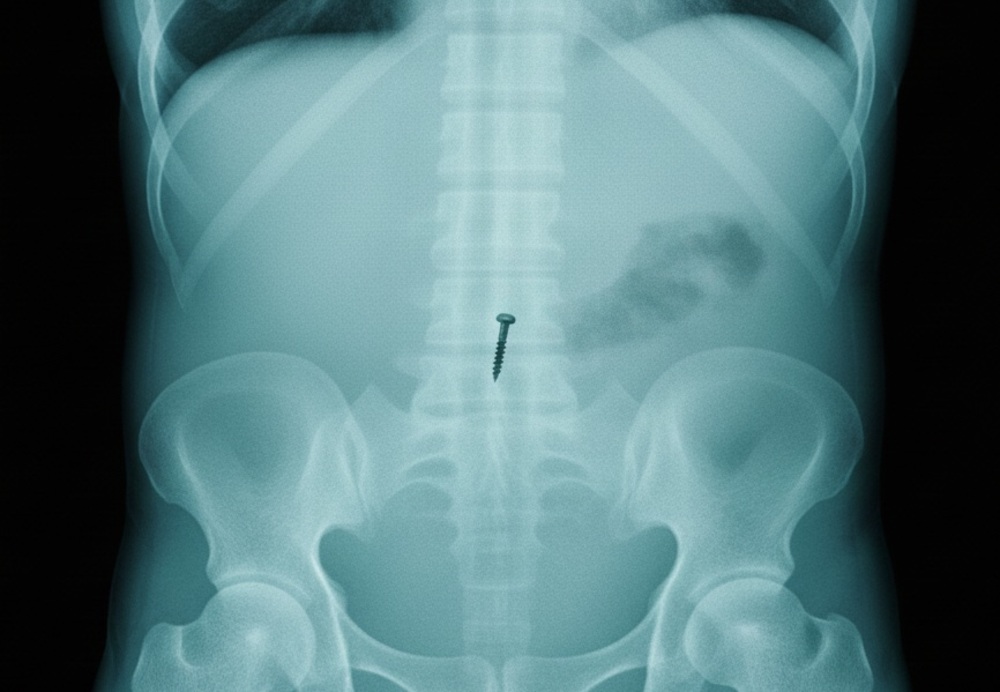

В Балаковскую городскую клиническую больницу на прошлых выходных экстренно госпитализировали десятилетнюю девочку, проглотившую гвоздь.

Как сообщили в пресс-службе медучреждения, врачи успели извлечь острый предмет до того, как он повредил внутренние органы. Сейчас ребёнка уже выписали домой.